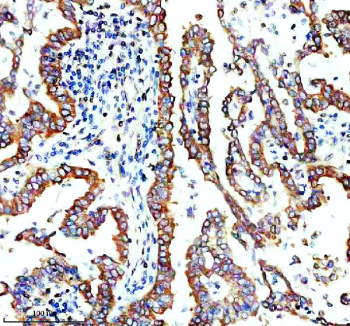

Immunohistochemical staining of TMEM173/STING using anti-STING1 antibody. TMEM173/STING was detected in a paraffin-embedded section of human lung cancer tissue. Heat mediated antigen retrieval was performed in EDTA buffer (pH 8.0, epitope retrieval solution). The tissue section was blocked with 10% goat serum. The tissue section was then incubated with 2 ug/ml rabbit anti-STING1 antibody overnight at 4oC. Peroxidase Conjugated Goat Anti-rabbit IgG was used as secondary antibody and incubated for 30 minutes at 37oC. The tissue section was developed using an HRP secondary and DAB substrate.